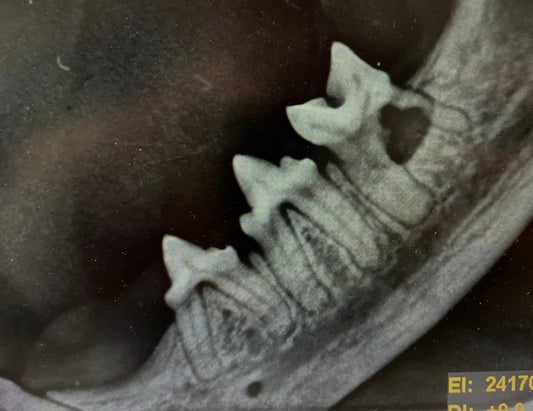

Neu bei uns! Dentales RöntgenWir freuen uns, nun auch dentale Röntgenbilder anfertigen zu können! Damit können wir die Diagnostik und Behandlung von Zahnerkrankungen noch genauer durchführen und individuell anpassen. Neu bei uns! Dentales RöntgenWir freuen uns, nun auch dentale Röntgenbilder anfertigen zu können! Damit können wir die Diagnostik und Behandlung von Zahnerkrankungen noch genauer durchführen und individuell anpassen.